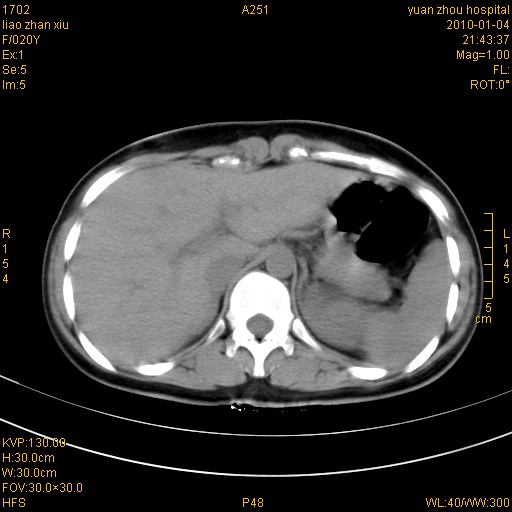

标题: CT23985:F20Y 外伤典型病例 [打印本页]

标题: CT23985:F20Y 外伤典型病例

左肾挫伤,包膜下积血。

左肾挫裂伤伴肾被膜下积血!另:肾周筋膜增厚!

1)左肾包膜下血肿。2)左侧肾挫伤可能;建议:行ct增强扫描检查。3)腰椎左侧横突骨折。

左肾挫伤,包膜下积血,l3、4左侧横突多发骨折。

双侧肾胞膜下出血,左侧较多。l3、4左侧横突多发骨折。

1、左肾挫伤,包膜下积血;

2、l3、4左侧横突多发骨折;

3、腹腔积气,考虑肠管破裂?

左肾挫伤,包膜下积血,L1、2、3、4左侧横突多发骨折。